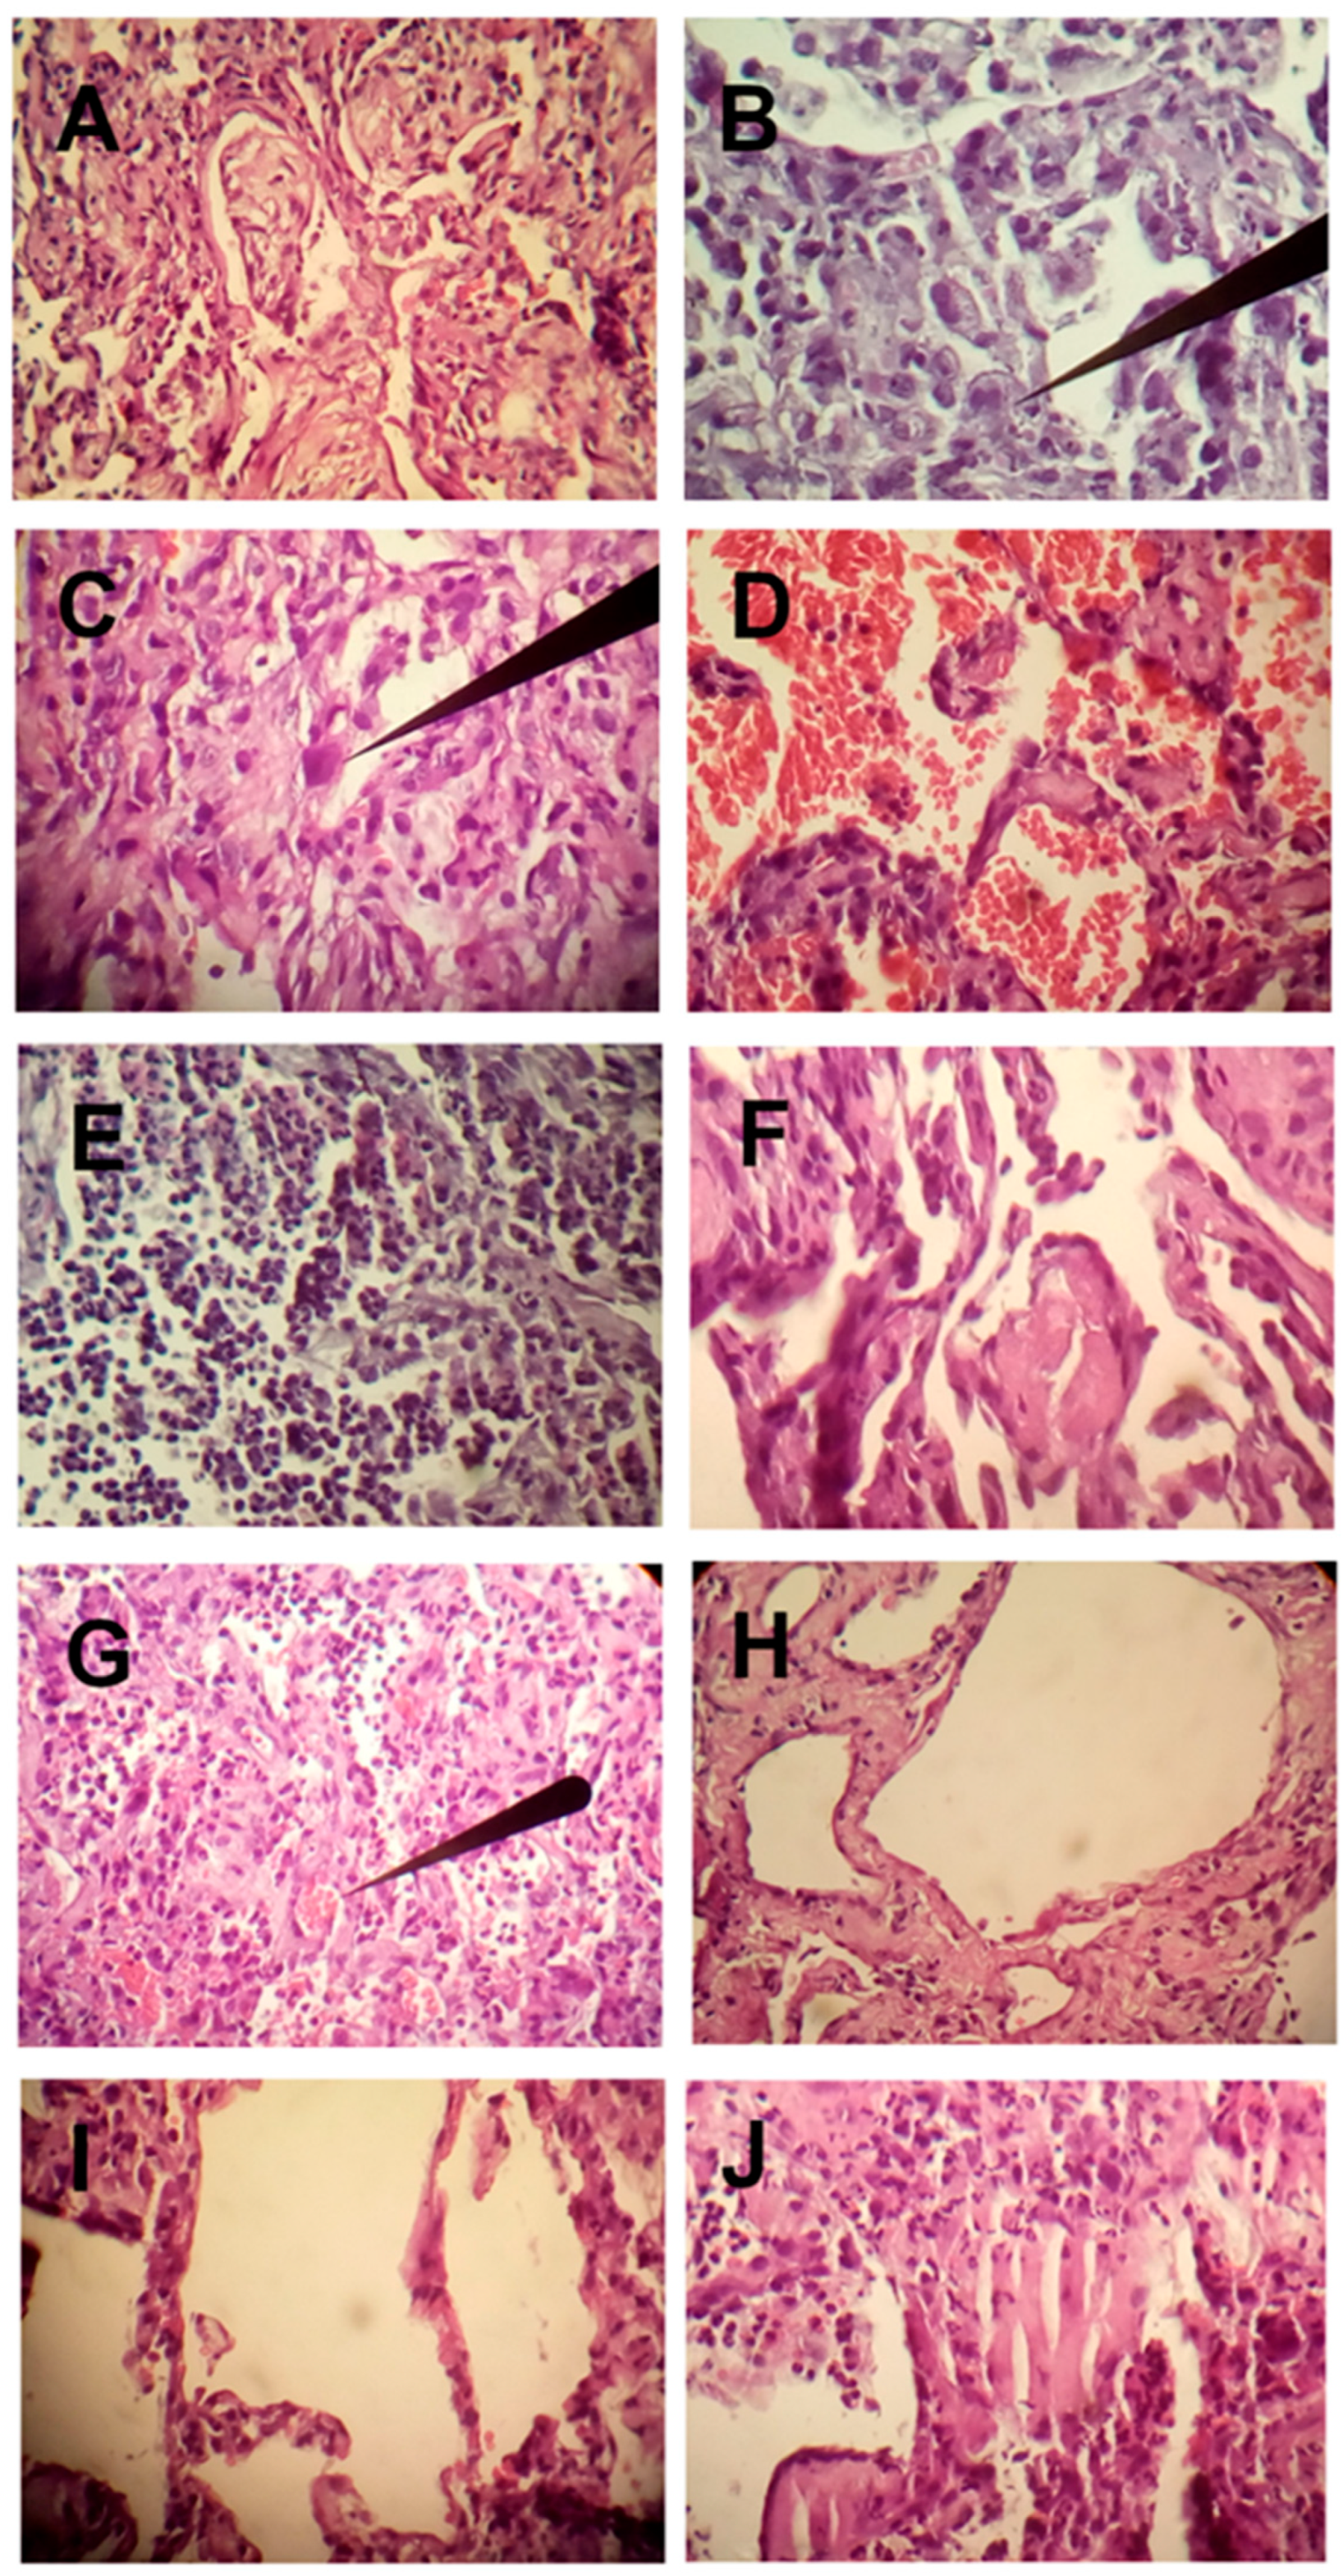

The histopathological findings of 19 patients who died from severe pneumolysis resulting from COVID-19 and adult respiratory distress syndrome in the intensive care unit of the General Hospital of Ecatepec, of the Health Institute of the State of Mexico, Mexico, are presented as preliminary findings (Figure 5). The time from initiation of mechanical ventilation to death averaged 16 days. Ultrasound-guided lung biopsies were performed immediately postmortem. The most important manifestation at the time of death, in addition to refractory hypoxemia, was CO2 retention (hypercapnia), with an average arterial blood gas CO2 of 90 mmHg (torr), confirming the pathophysiology (Figure 6 at sea level and Figure 7 at high altitude). Among the most important histopathological findings, as shown by the following photomicrographs, were changes associated with diffuse alveolar damage (DAD). This is a general term used in relation to ARDS [35], but since we are now dealing with a new highly lethal pathology, a more precise terminology is required. This is what we define as pneumolysis, an inflammatory process characterized by lung tissue derangement with alveolar collapse, hyaline tissue formation, microhemorrhages, microabscesses possibly due to superinfection, infiltration of polymorphonuclear cells and monocytes, and a repair process with organizational changes in fibrinoid deposits, early fibroblastic interstitial fibrosis, and Masson’s bodies. Additionally, fibroblast proliferation and collagen deposition with intense septal and para-septal reparative fibrosis can be observed, which significantly thicken the alveoli and explain the decreased gas-exchange area and hypercapnia in pneumolysis. Other authors have found the virus only in the acute initial stage of lung compromise and not in the progressive late stage, where there was an immune response that possibly cleared the virus [36]. However, in our studies, the presence of reactive pneumocytes with nuclear atypia (nucleomegaly, hyperchromasia) is striking [28], indirectly indicative of active viral replication, even at the time of death. This is a very important observation, as it shows the pneumocytes, due to SARS-CoV-2 aggression, with RNA inoculation within and changing the metabolite production code to replicate itself. This means that either the emergency cellular condition gives rise to nuclear.

Figure 5.

(A) Masson bodies. Note the hyaline border fixed to the alveolar walls. (B) Intra-alveolar macrophages (arrow). (C) Alveolar coating cells with nuclear atypia, reactive pneumocytes, and reparative fibrosis (arrow). (D) Intra-alveolar hemorrhage. Presence of intra-alveolar and septal interstitial polymorphonuclear cells. Note the thickening of the intra-alveolar septum with moderate inflammatory infiltrates. (E) Intra-alveolar abscesses. (F) Fibrinoid deposits. (G) Microthrombus (arrow). (H) Intense septal fibrosis. Note, in the lower part of the larger alveoli, the presence of a remnant of a hyaline membrane. (I) Area of alveolar rupture (emphysema). (J) infiltrated by pneumocystis (opportunistic infection). Photo and pathological analyses were performed by Dr. Felipe de Jesus Montelongo (Head Intensive Care) and Dr. Manuel Gabriel Romo Sanchez (Pulmonary Pathology specialist) from the Hospital General de Ecatepec Las Americas, ISEM, México.

Alterations or the virus itself alters the nuclei, which needs to be further investigated. The replication process is carried out in the lysosomes, the endoplasmic reticulum, and the Golgi complex [37]. Likewise, there are heterogeneous areas of alveolar rupture. These changes were observed in 100% of patients. Other findings included intra-alveolar hemorrhage in 54% of the patients and microabscesses by bacteria, fungi, and other opportunists such as pneumocystis in 50% of the patients, a finding of great importance since it was thought that most of the patients had died from pneumonia associated with mechanical ventilation. Likewise, microthrombi were found in 37% of the patients, which is not consistent with previous studies. It should be noted that 100% of the patients had prophylactic anticoagulation at the time of death.

We can conclude that the patients presented an active process of cell destruction (pneumolysis) due to active viral replication, with persistent infiltration of inflammatory cells and a continuous repair process but with reactive fibrotic activity that was so intense that it ultimately led to death. Furthermore, these multiple findings, with superimposed opportunistic infections, complicated the evolution of the disease.